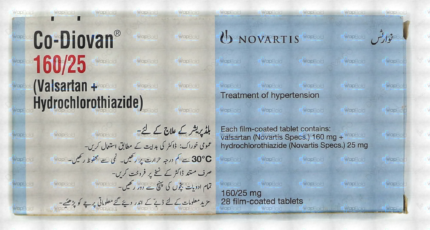

Co-Valstar Tablets 160Mg/25Mg (1 Strip = 7 Tablets)

₹646.80 Original price was: ₹646.80.₹614.50Current price is: ₹614.50.

- Variations: Strip

- Discount Amount On Strip: £32.3

- Prescription Required: Yes

- Strip: £646.0

- Used For: Hypertension

- Brand: C.C.L (Pvt) Ltd .

- Min Order Quantity: 20 units

- Min Order Price: ₹12936.00

Co-Valstar Tablets 160Mg/25Mg – 7 Tablets per Strip

Discover the power of Co-Valstar Tablets, designed to provide effective relief with each dose. Each strip contains 7 tablets, ensuring you have the right amount of medication at your fingertips. With a combination of 160mg and 25mg, these tablets are tailored to meet your needs. Whether you’re managing symptoms or seeking relief, Co-Valstar Tablets are here to help you feel better.

Key Features:

- Convenient Packaging: 7 tablets per strip for easy dosing.

- Effective Relief: Formulated with 160mg and 25mg for optimal results.

- Trusted Quality: Reliable and consistent medication for your well-being.

Experience the difference with Co-Valstar Tablets. Order now and take the first step towards better health.